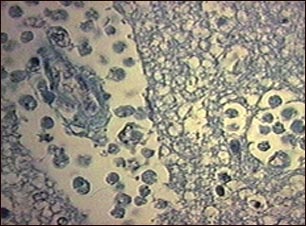

Absceso cerebral amebiano

La amebiasis es comúnmente una infección del tracto intestinal, pero puede diseminarse e infectar otros órganos, tales como el hígado o el cerebro; siendo la infección de este último posiblemente mortal. En esta lámina se puede observar la ameba en una muestra de tejido cerebral. La amebiasis es una infección grave para las personas inmunocomprometidas. (Cortesía de los Centros para el Control y la Prevención de Enfermedades -CDC- de los Estados Unidos)